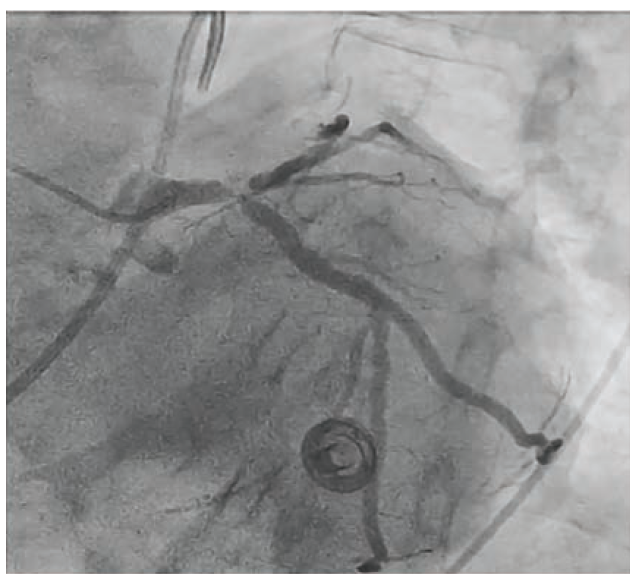

Based on the above assessment with IVUS, we elected to proceed with orbital atherectomy (Diamondback 360 orbital atherectomy system, Abbott Vascular) of the LAD, before which the LCX wire was removed and the LAD wire was swapped for a ViperWire with Flex Tip (Abbott Vascular) using a 1.7F distal tip FINECROSS® M3 Coronary Micro-Guide Catheter (Terumo Interventional Systems). Orbital atherectomy was performed with 4 passes at 80,000 RPM. The LAD (Figure 3) was treated with a 3.0 mm x 15 mm Takeru NC balloon. The LCX was rewired with the same Runthrough wire and a double kiss (DK) crush technique was used to stent the LM distal bifurcation with two Xience Skypoint drug-eluting stents (Abbott Vascular) (Figure 4 highlights the sizes and steps of the DK crush technique). IVUS assessment demonstrated well-opposed and well-expanded stents from the LAD and LCx into the distal LM (Figure 5).